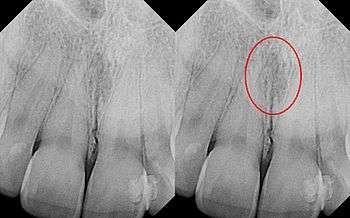

Identical images with heart-shaped radiolucency highlighted in right film.

The nasopalatine duct cyst (abbreviated NPDC) occurs in the median of the palate, usually anterior to first molars. It often appears between the roots of the maxillary central incisors. Radiographically, it may often appear as a heart-shaped radiolucency. It is usually asymptomatic, but may sometimes produce an elevation in the anterior portion of the palate. It was first described by Meyer in 1914.[1]

As a cyst, the nasopalatine duct cyst requires histological analysis for a definitive diagnosis. Radiographically, the nasopalatine cyst appears as a well-demarcated round, ovoid, or heart-shaped structure presenting in the midline of the maxilla.[5]